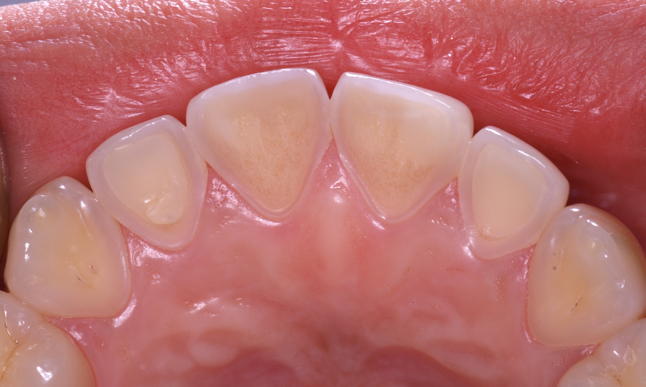

Another intrinsic factor is the patient's gastric acid entering the oral cavity. The source of intrinsic stomach acid may range from rumination or gastroesophageal reflux to chronic alcoholism, pregnancy, or vomiting caused by anorexia nervosa or bulimia nervosa.13 Figure 1 through Figure 3 show the radiographic presentation and clinical examples of dental erosion in advanced stages in the same patient caused by the combination of bulimia nervosa and chronic alcoholism.

Fig 2. Facial erosion of maxillary (Fig 2) and mandibular (Fig 3) anterior teeth.

Figure 2